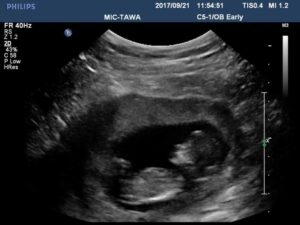

I scheduled an appointment at the diabetes clinic to discuss further treatment on Valentine’s day. While there, I actively started going into labor. I was only 33 weeks pregnant, so everyone went into a panic and rushed me to the labor and delivery ward in the same hospital. The doctors couldn’t decide whether or not to stop my labor, so they admitted me for observation. I had nothing with me and had left my daughter with my mom thinking it couldn’t possibly be labor. I spent the night having irregular contractions but the baby was still stable. The next day the on-call OB sent me for an ultrasound around 2 p.m., which took 2 hours. I didn’t think anything was out of the ordinary then either. I was actually expecting to get released to go home and be on bed rest, but then 2 separate radiologists came to review my ultrasound – I knew then there was something going on.

They wheeled me out the room to wait for the porter to take me back to my room. What I didn’t know was that they had seen a bright spot on my son’s liver and that his heart was enlarged. Next thing I knew, two surgical nurses where rushing me up to pre-op and telling me to get my husband there now. My husband made the 20-minute drive from his work in 5 minutes. He only barely arrived. Tthey were wheeling me in while he was changing into scrubs. From the time they decided I need to deliver, to actual delivery, it was a half hour.